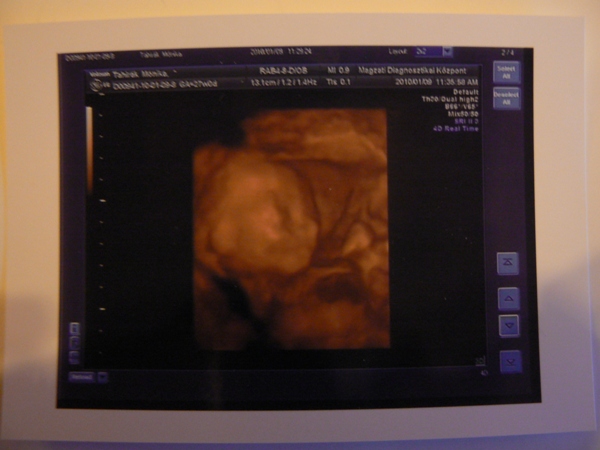

Na megjöttünk!FANTASZTIKUS volt! :lol: Nagyon megérte.

Ercsikati:A magzati diagnosztikai központba voltunk.

Caysee:Nekem se írt semmit a kiskönyvembe.Viszont most megkérdeztem a dokit aki a 4D-t csinálta és azt mondta hogy általában a 20. hét után kezdik el nézni.Én viszont megnyugodtam mert mellső fali lepényem van,viszont magasan van a méhszáj fölött.

A pisiről annyit hogy nekem egyszer kellett október elején a vérvétellel együtt,miután kiderült hogy terhes vagyok,és azóta se kellett egyszer sem vinnem!Kész káosz,akkor ez hogy van?

Még annyit a 4D-ről,hogy kaptunk egy 12 perces videófelvételt,1db kinyomtatott kisképet(amit fel is teszek),plusz a leletemnél is van 4 kép egymás alatt,amiket a felvétel alatt csinált.Megpróbáljuk majd azokat beszkennelni és akkor még lesz több kép is.Nagyon izgett mozgott,alig akarta megmutatni magát,szinte végig takarta a kis pofiját,de azért egyszer kétszer el tudtuk csípni :lol: Valamint a mi kis szégyenlős babónk a "lényeget" sem akarta nagyon megmutatni,de a furfangos doki bácsi megoldotta,és alulról a lába közé lestünk :lol: Minden szervét részletesen megvizsgálta,mindent a helyén talált,még a szájacskáját is megnézte.Meg voltam vele elégedve,bár manócska nagyon ellenállt!Az utolsó 5 percben a pofija előtt tartotta a kezét.

Na felteszem azt az egy képet amit idáig sikerült megcsinálnunk: Kép Balázs 4D-s felvételen